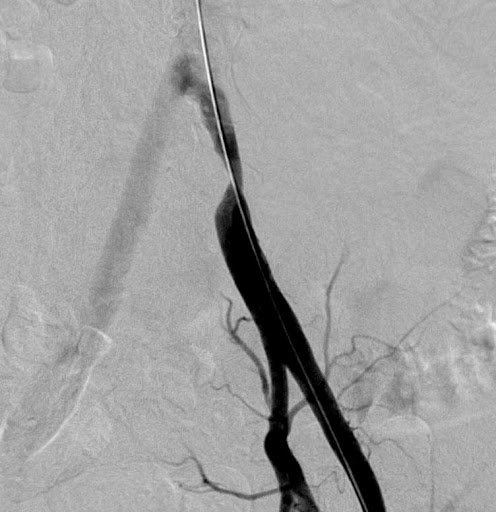

Angioráfia